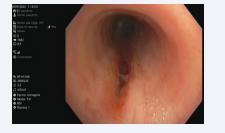

The following two days after bronchoscopy, the patient remained clinically and radiologically stable; a reduction in the amount of subcutaneous emphysema and pneumomediastinum was noticed. Therefore, in accordance with the Intensive Care Unit and due to stable conditions, on VI day of hospitalization, she was transferred to our Thoracic Surgery department, where a new revaluation with bronchoscopy was performed. The wellknown tracheal laceration of the ‘‘pars membranacea’’ was completely covered by a layer of fibrin [Figure 4].

Tracheal laceration covered by fibrin.

Figure 4: Tracheal laceration covered by fibrin.

The patient underwent two follow-up bronchoscopies, one 3 days after discharge and the other after one month. The first one showed that the lesion appeared to be in almost complete repair, in the absence of continuous solution [Figure 5]. After one month, the recent middle third tracheal lesion appeared completely repaired and re-epithelialized with minimal hyperemia, in the absence of continuous solution [Figure 5].

Complete tracheal lesion repair at one month bronchoscopy  control.

Figure 5: Complete tracheal lesion repair at one month bronchoscopy control.